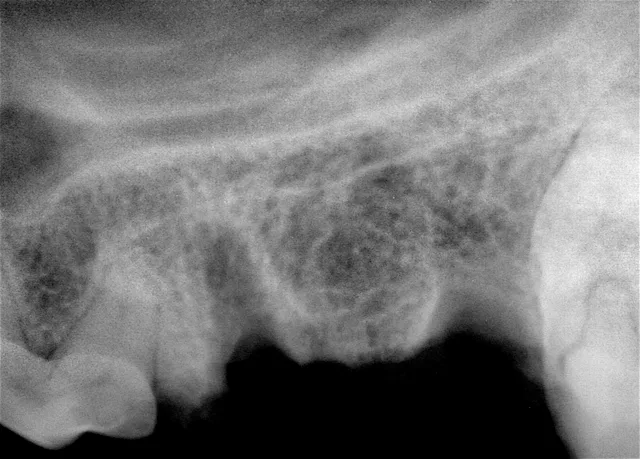

Step 14

The site is radiographed postoperatively (A) and the mucoperiosteal flap is closed using absorbable suture in a simple interrupted pattern (B).